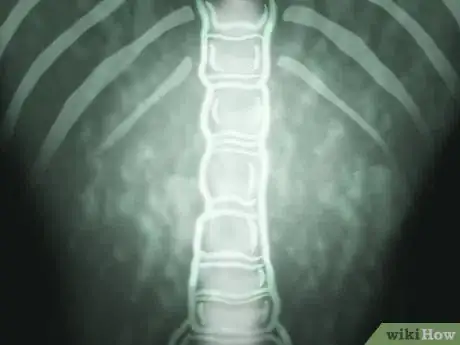

Scoliosis is an abnormal curvature of the spine, typically in the mid-back or thoracic area, that affects about 7 million people in the United States.[1] Scoliotic curves can deviate to the right or left and usually involve some twisting or rotation of the vertebrae (spinal bones). Scoliosis surgery for adolescents is only recommended when their curves are greater than 40 – 45 degrees and progressing, and only for adults with curves greater than 50 degrees.[2] The operation for scoliosis is a spinal fusion (essentially a "welding" process) that typically involves metal rods, wires and/or screws. Like any significantly invasive surgery, it can be physically and emotionally traumatic. As such, specific steps should be taken to appropriately deal with the repercussions.

1Learn what scoliosis is. From a side (lateral) view, the spine is normally curved much like the letter "S" in order to best support the body, allow for flexibility and to protect the spinal cord. However, when viewed from behind (posterior), the spine should appear fairly straight and not deviate too much to either side. Many people have a few degrees (less than 10) of lateral deviation that's typically ignored and not diagnosed as scoliosis because it doesn't cause any problems. There are many potential causes of scoliosis, including congenital spine deformities (present at birth), spina bifida, cerebral palsy, muscular dystrophy, spinal infection, trauma from accidents and certain spinal tumors, although in more than 80% of cases the cause is unknown, or idiopathic.[3]

2Realize that scoliosis doesn't always require surgery. Scoliosis is relatively straightforward to measure on spinal x-rays, but curves are not considered significant until they are greater than 25 – 30 degrees.[5] As such, mild and moderate curvatures are not even considered for surgery, regardless if they cause discomfort or not. Mild-to-moderate scoliosis may cause some noticeable deformity, but it's usually too difficult to tell with clothes on. In many cases, the diagnosis of scoliosis sounds much worse than how the condition actually presents or any symptoms that it may cause. People with mild-to-moderate scoliosis live normal lives and can even become top-class athletes, so don't get overly upset or concerned with an initial diagnosis of scoliosis.

3Recognize when surgery is needed. Although a scoliotic curve is considered significant at around 30 degrees, that's still not enough to warrant surgery. It's not until a curve reaches 40 degrees in an adolescent that a doctor starts to even consider surgery, and then only if there are signs of fairly rapid progression and/or serious symptoms. However, as curves approach 45 – 50 degrees in a younger teenager, then most doctors recommend surgery not only to combat the growing deformity for cosmetic reasons, but also to reduce the risk of disabling symptoms. Severe scoliosis (a curve greater than 80 – 90 degrees) can be disabling because it pushes the rib cage against the lungs and heart, making it difficult to breathe and forcing the heart to work harder.[7]